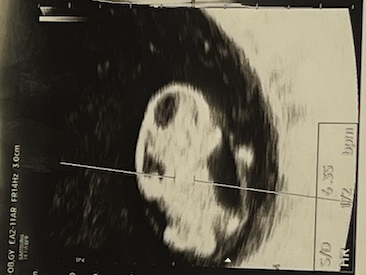

그렇게 초조한 마음을 버티고 버텨 드디어 검진날. 다행히 질 초음파를 통해 젤리곰이 된 *도담이를 만날 수 있었고 심장도 콩캉콩캉 잘 뛰고 있었다. (태명은 이리저리 고민하다 건강하고 탐스럽게 자라라는 의미를 담은 "도담"으로 결정했다.) 며칠 전 밤 배에 손을 올리고 있는데 뭔가 손에서 심장박동이 느껴지는 것만 같아서 자기야. 심장소리가 느껴지는 것 같애. 라고 했었는데 혹시나 해서 제가 심장박동을 느낄 수도 있나요?라고 물어봤더니 하하하. 아니요. 전혀요.라고 말씀하시는 선생님의 단호박에 머쓱..

스크린샷 2025-07-08 오후 8.39.31.png 젤리곰 시절의 도담이. 흡사 둘리 같애서 너무 귀엽잖아..!